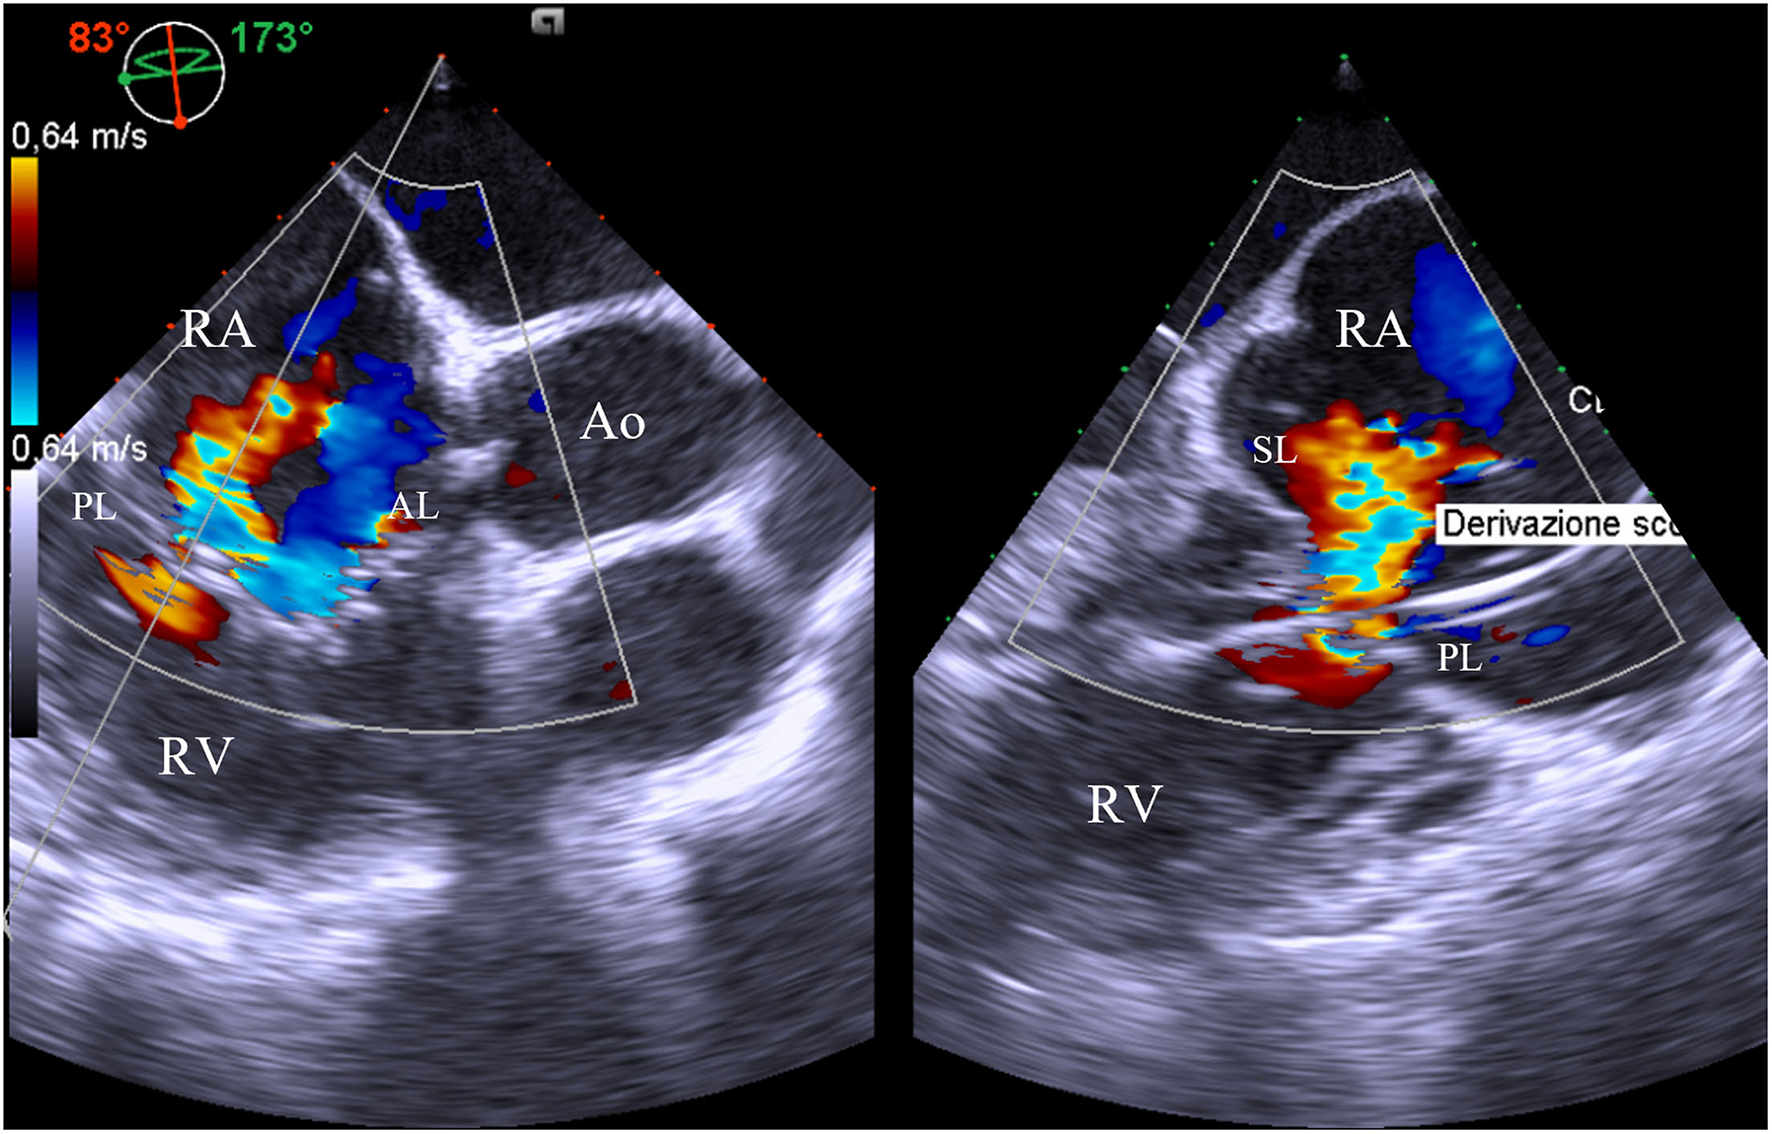

Transesophageal echocardiography is the second-line imaging modality for the assessment of TV anatomy in patients with TR, even if the anterior position of the valve can limit the examination. Nevertheless, TEE allows obtaining imaging from several depths (mid-esophageal, distal-esophageal, shallow transgastric, and deep transgastric views) and multiplane angles. The four-chamber view (0–0°) and the alternative four-chamber view (160–180°) permit the visualization of the septal and typically the anterior leaflet; the posterior leaflet can also be visualized by changing probe angulation. Simultaneous biplane imaging may clarify which leaflet is imaged because the anterior leaflet is usually adjacent to the aorta, whereas the coronary sinus is the marker for the posterior leaflet. Other useful information for a comprehensive TV assessment may be achieved by a mid/deep esophageal RV inflow/outflow view in multiplane (60–100°), which crosses the coaptation between the septal and the posterior leaflet (near the lateral annulus) and the septal and anterior leaflet (near the aorta) (14) (Figure 1).

Figure 1

Mid-esophageal right ventricle inflow/outflow view with orthogonal multiplane, which crosses the coaptation between the septal and the posterior leaflet. At this level, it is identified the major origin of the jet, as well as the presence of pacemaker lead interfering with mobility of the posterior leaflet. AL, anterior leaflet; Ao, aorta; PL, posterior leaflet; RA, right atrium; RV, right ventricle; SL, septal leaflet.